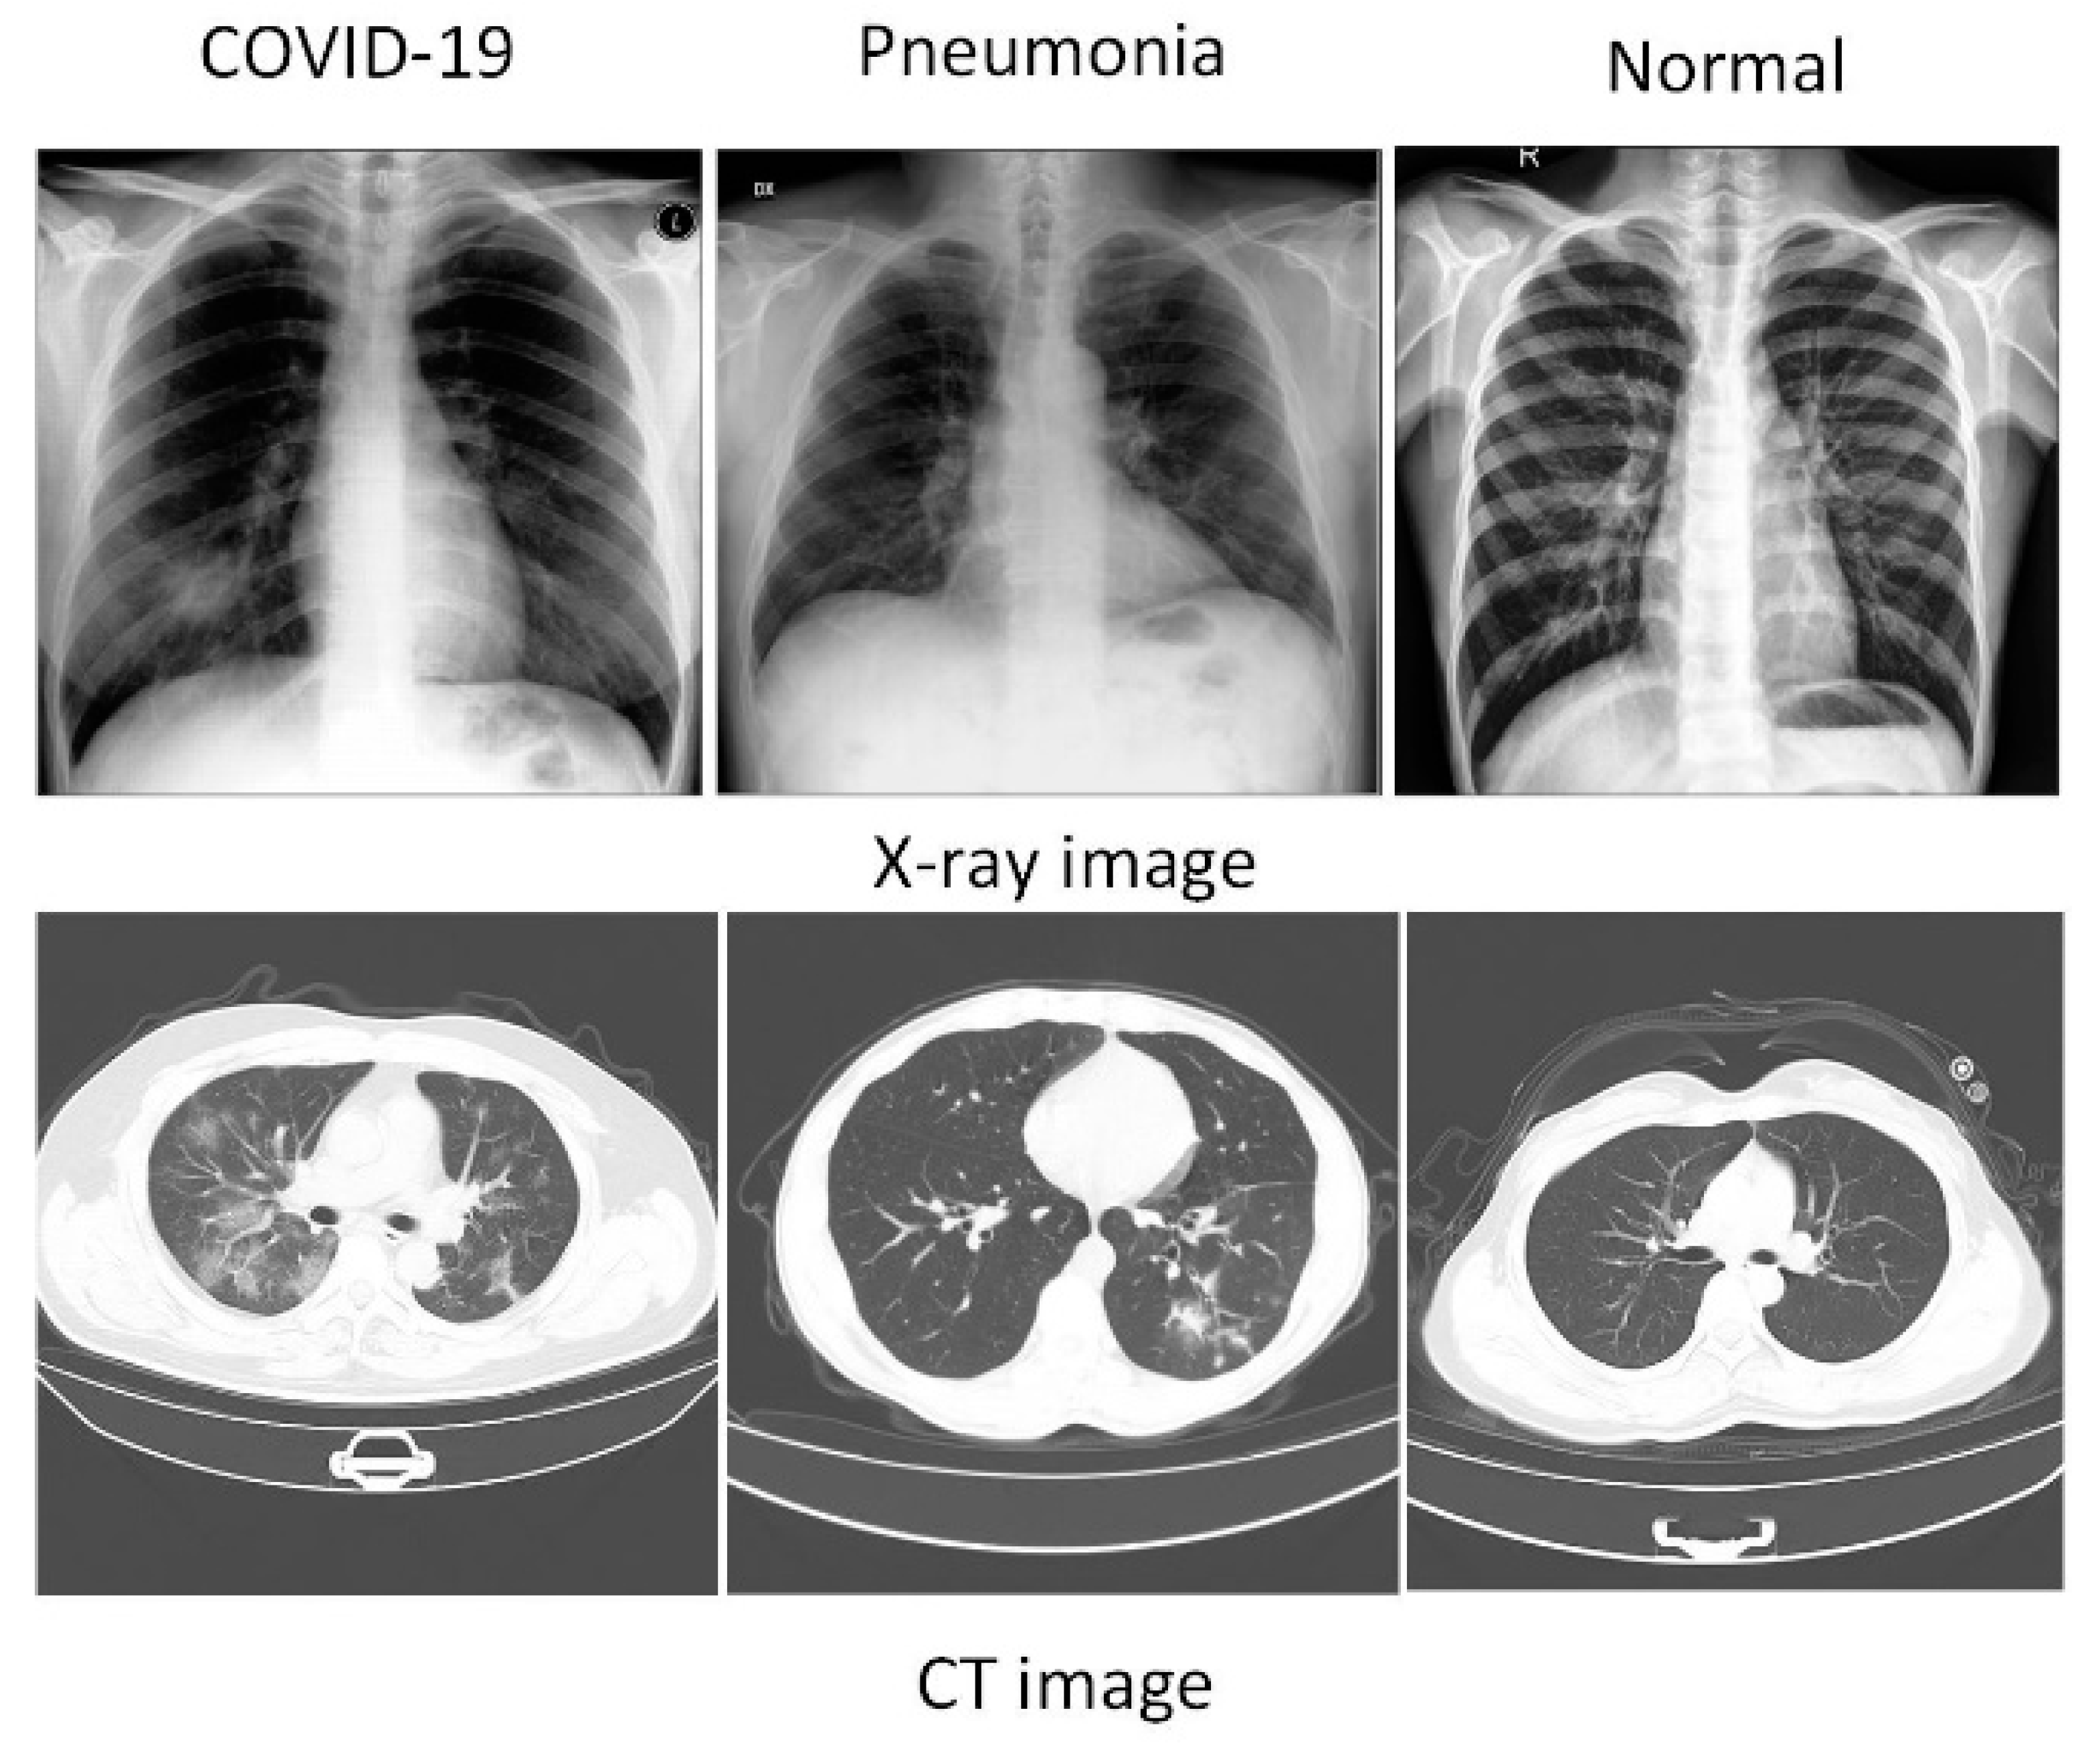

- This review provides a more comprehensive review of classification and segmentation method on CT and X-ray datasets of deep learning imaging diagnostic methods for COVID-19.